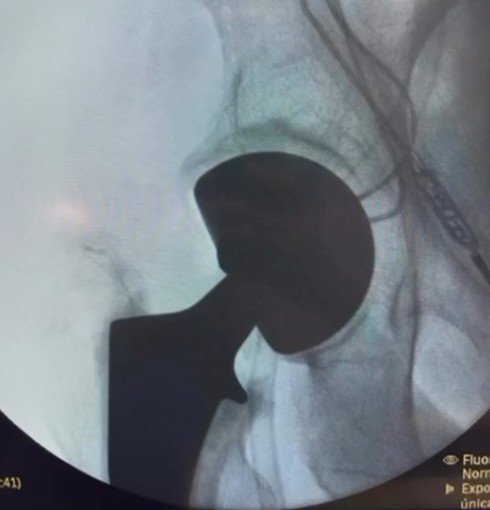

El fresado acetabular

-Se recomienda utilizar herramientas fresadores con “offset” o curva que nos permitan fresar sin el efecto de palanca o leva, que nos ocsaiona tanto la herida reducida como el fémur.

-El fresado se hace bajo fluoroscopia, cuidando la orientación final del implante a 45° inclinación acetabular y 15° de anteversión.

-Las reglas de fresado cambian un poco dependiendo del implante que se usa, en cuanto a profundizar o incluso subir o bajar de diámetro de la raspa.

-Este punto es clave, la orientación del fresado y colocación del implante definitivo debe ser la misma para lograr una fijación a presión “PressFit” ideal.